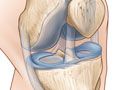

Generalidades de la prueba

La resonancia magnética es una prueba que se realiza con una máquina de gran tamaño que utiliza un campo magnético e impulsos de energía de ondas de radio para obtener imágenes de la rodilla. Los músculos, ligamentos, cartílagos y otras estructuras articulares suelen verse mejor con una resonancia magnética. En muchos casos, una resonancia magnética proporciona información sobre estructuras del cuerpo que no pueden verse tan bien con una radiografía, una ecografía ni una tomografía computarizada.

Para una prueba de resonancia magnética, se le coloca dentro del imán para que su rodilla quede dentro del fuerte campo magnético. Una resonancia magnética puede detectar cambios en la estructura de órganos u otros tejidos. También puede encontrar daños en los tejidos o enfermedades, como una infección o un tumor. Las imágenes de una resonancia magnética son imágenes digitales que pueden guardarse y almacenarse en una computadora para su estudio posterior. Las imágenes también pueden revisarse a distancia, por ejemplo en una clínica o en un quirófano. También pueden hacerse fotografías o placas de las imágenes seleccionadas.

La resonancia magnética de la rodilla se realiza para:

• Comprobar la causa de un dolor de rodilla inexplicable o de que la rodilla ceda sin motivo.

• Encontrar problemas en la articulación de la rodilla, como artritis, tumores óseos o infección, o cartílagos, meniscos, ligamentos o tendones dañados.

• Averiguar si es necesaria una artroscopia de rodilla.

La resonancia magnética también puede detectar una fractura ósea cuando las radiografías y otras pruebas no dan una respuesta clara. La resonancia magnética se realiza con más frecuencia que otras pruebas para detectar determinados problemas óseos y articulares.